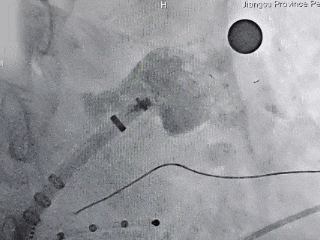

MemoLefort封堵器展开后DSA下造影评估

输送鞘轴向不佳,半回收封堵器

半回收封堵器,调整输送鞘方向

边造影边半回收,调整位置后重新退鞘,确保轴向,减少露肩